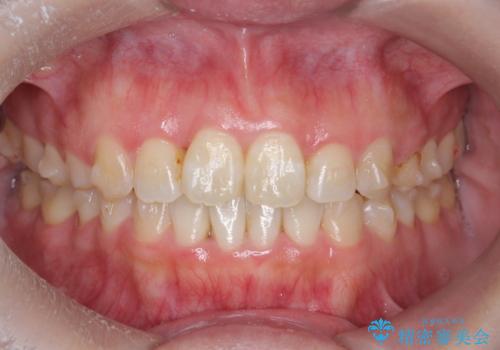

- 前歯のねじれを改善したい、と矯正治療を希望され来院されました。

上下の歯のがたつきを改善するマウスピース矯正治療と、下顎に見られる大きな骨隆起を外科的に除去する治療計画を進めていきます。